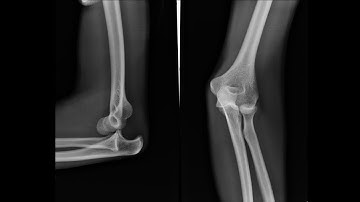

Dislocation Reduction Elbow (sample) - proceduresconsult.com